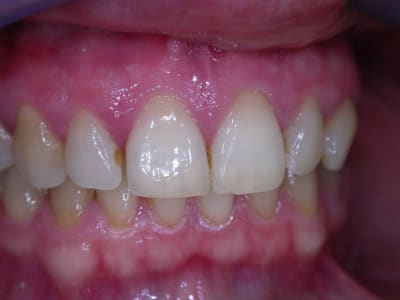

examen buccal .........voir les photos ........après ........ca vient

examen radio .........après ca vient.......

Bon controle de plaque, pas de tartre ni de colorations, inflammation en palatin seulement...